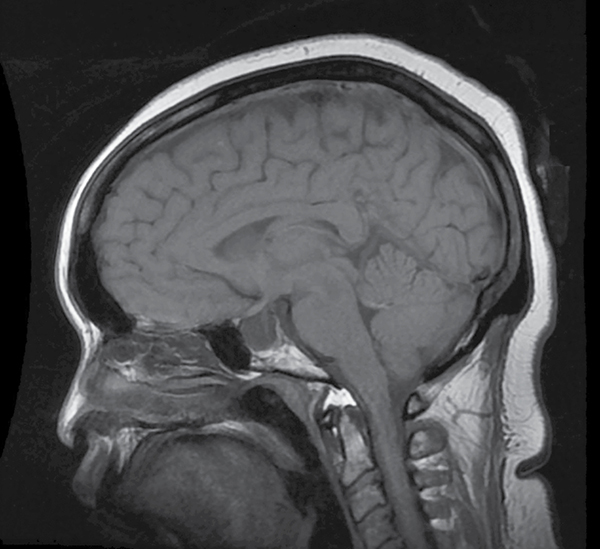

Az idiopathiás intracranialis hypertensio (IIH) – korábban elterjedt nevén benignus intracranialis hypertensio, vagy pseudotumor cerebri – a kétoldali papillaödéma eredetének kizárásos diagnózisa, amelyet a Thurtell áttekintő cikkében is jegyzett, módosított Dandy-kritériumok alapján akkor állapíthatunk meg, ha a beteg éber és kommunikációképes, az intracranialis hypertensio klinikai jeleit és tüneteit látjuk neurológiai gócjelek együttes fennállása nélkül (kivételt képez a VI. agyideg paresise), normál labordiagnosztikai paraméterek mellett és per definitionem megjelölhető eredet hiányában. A tünetek közül a legjellemzőbb a fejfájás (85%), tranziens látótérhomályok (70%) és pulzusszinkron tinnitus (50%), azonban számos esetben az állapot teljesen tünetmentes, klinikai jeleként a szemfenéken látható, jellemzően kétoldali papillaödéma rutin szemészeti szakvizsgálat során is észlelésre kerülhet. A papillaödéma együtt járhat csíkolt vérzések, gyapottépés gócok, exudatumok és papillomacularis subretinalis folyadék megjelenésével. Az intracranialis nyomás lumbálpunkció elvégzését követően manometrikusan mérhető – e beavatkozás a liquor lebocsátása révén terápiás hatású is lehet. Felnőttkorban 20 H2Ocm (15 Hgmm) feletti értéket tekinthetünk emelkedettnek. A nyomásfokozódás radiológiai jelei szubtilisek, ilyen a liquor által kitöltött ún. empty sella (1. ábra).

Forrás: https://radiopaedia.org/cases/empty-sella-1